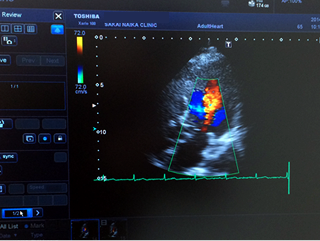

心臓超音波検査(心エコー)

人の耳には聞こえないほどの高周波数の超音波を心臓に発信して、心臓の動きを観察します。

心臓の大きさ、動き、弁膜症の有無などを簡単に、正確に診断することが出来ます。

X線撮影やRI検査のように放射線による被曝の心配がありませんので安心して受けることができます。

心臓超音波画像診断装置

また、心臓の大きさや壁の厚さ(心臓肥大の有無)、弁の形や動きなどがわかります。カラードップラー法を行なうと、心臓の中の血液の流れを映し出すことができ、弁膜症などの異常を発見できます。